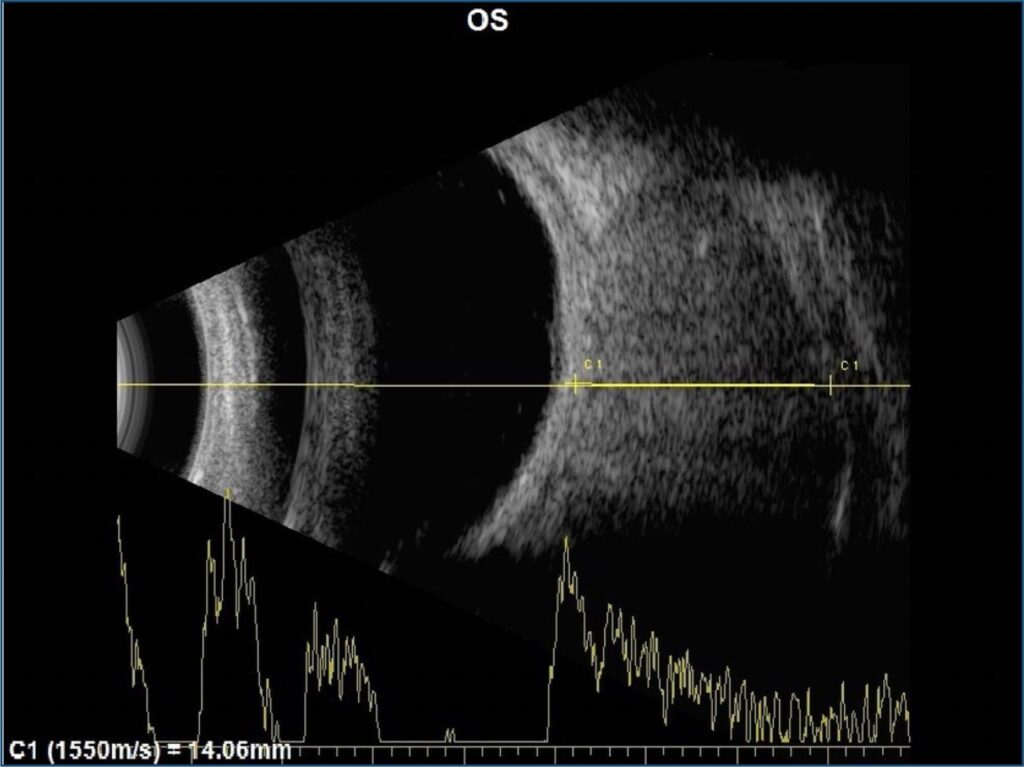

Association between progressive hyperopia and cavernous hemangioma

Cavernous hemangiomas are benign malformations of vascular origin, generally well circumscribed and with slow growth. These lesions can be asymptomatic, being discovered unintentionally on imaging exams, or symptomatic, indicated mainly by the presence of proptosis, diplopia, and visual disturbances due to compression of the optic nerve. Preoperative evaluation is essential and makes the use of imaging exams essential for carrying out adequate planning, with computed tomography and magnetic resonance imaging being the first choices. Treatment can be conservative or surgical, depending on the case, and open therapy usually involves endoscopic orbitotomy. The objective of the present study is to report the case of a patient with progressive hyperopia associated with intraconal cavernous hemangioma and show common symptoms from clinical practice that can mask pathologies when not investigated correctly.